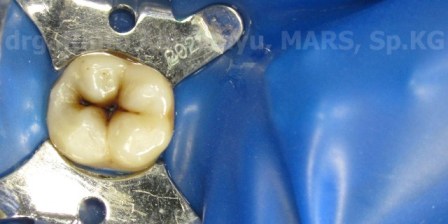

Pengecekan oklusi dilakukan dan kelebihan bahan tambal saya buang menggunakan bur super fine (strip kuning) dan dilakukan pemolesan menggunakan Diacomp Eve Twist.. Pada restorasi ini saya tidak memakai staining atau color modifier….

This is the final result..

Pasien ketika ditunjukan hasilnya sangat puas… alhamdulillah…